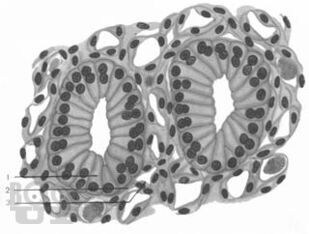

Диагностика микропрепаратов

Мустафина Л. Р. Диагностика микропрепаратов : Учебное пособие по общему и частному курсу гистологии для самоподготовки студентов лечебного и педиатрического факультетов / Л. Р. Мустафина, С. В. Логвинов, Е. Ю. Варакута. - Томск : Издательство СибГМУ, 2018. - 46 c. - Текст : электронный // ЭБС "Букап" : [сайт]. - URL : https://www.books-up.ru/ru/book/diagnostika-mikropreparatov-9283102/ (дата обращения: 16.02.2026). - Режим доступа : по подписке.

Учебное пособие предназначено для самостоятельной работы с микропрепаратами при подготовке к итоговым практическим занятиям по общему и частному курсу гистологии студентов I и II курсов лечебного и педиатрического факультетов.